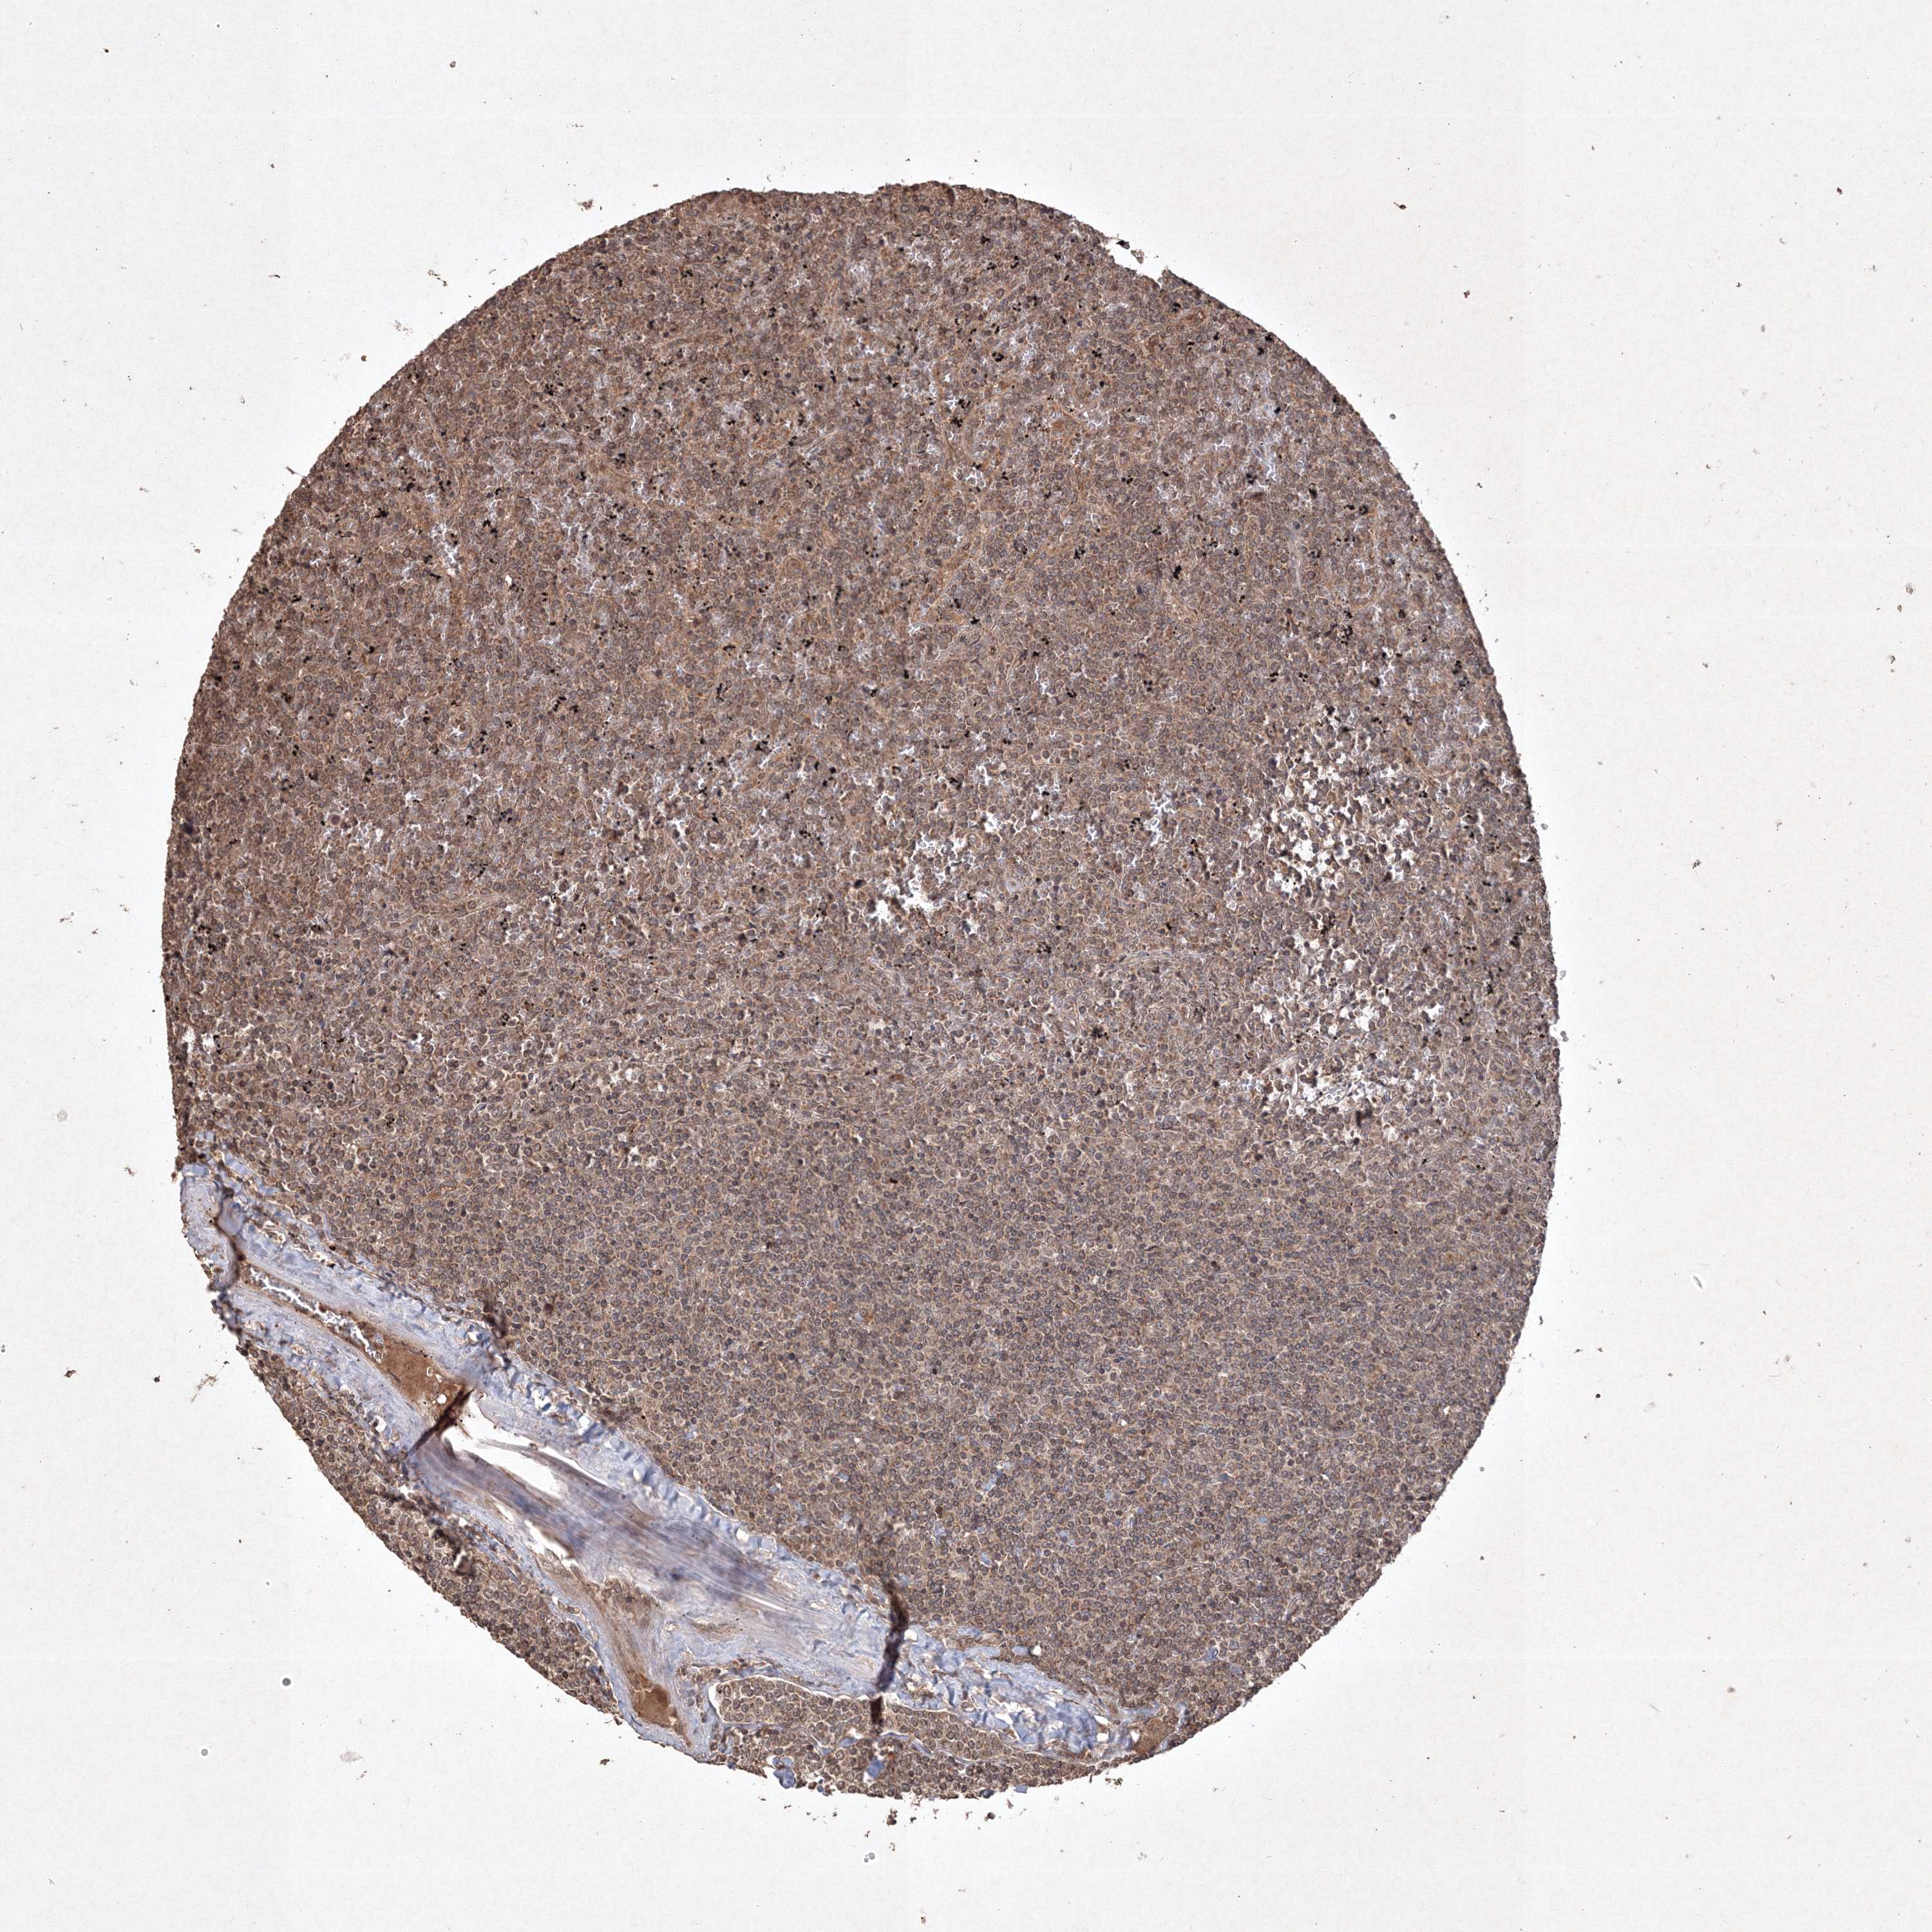

LYMPHOMA - Protein expressioni

A mouse-over function shows sample information and annotation data. Click on an image to view it in a full screen mode. Samples can be filtered based on level of antibody staining by selecting one or several of the following categories: high, medium, low and not detected. The assay and annotation is described here.

Each image is clickable and will lead to virtual microscopy that enables deeper exploration of all samples and also displays staining intensity scores, fraction scores and subcellular localization as well as patient and tissue information for each sample.

Antibody HPA038875

Staining

High

Medium

Low

Not detected

Intensity

Strong

Moderate

Weak

Negative

Quantity

>75%

75%-25%

<25%

None

Location

Nuclear

Cytoplasmic/membranous

Cytoplasmic/membranous,nuclear

Malignant lymphoma, non-Hodgkin's type, Low grade

Malignant lymphoma, non-Hodgkin's type, High grade

Hodgkin's disease, NOS